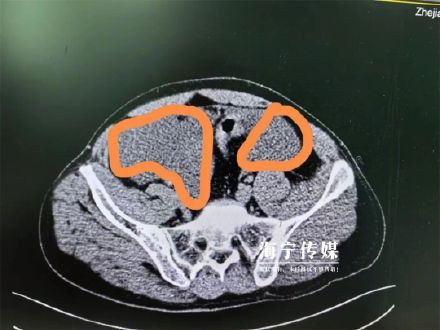

近日在浙江海宁,小陈与朋友喝酒解闷,大概喝了一斤多的白酒,喝完整个人迷迷糊糊的。也不知多了多久,小陈去上厕所时不慎摔了一跤,之后就发现怎么也排不出尿,而且腹部十分胀痛。连夜看了急诊,确诊为膀胱后壁的腹膜内破裂,相当于尿液全到肚子里面去了。医生立即为小陈进行了膀胱修补手术,但由于腹腔感染严重,手术后,小陈又被送进ICU治疗了五天,这才转危为安。

医生介绍,醉酒后,酒精抑制了神经中枢,让排尿感觉迟钝。当尿液充盈时,犹如充满水的气球,一旦有外力重击,如车祸、跌倒、高处掉落,就有膀胱破裂的风险。所以要谨记,喝酒切莫贪杯,更不要憋尿。(大潮网)